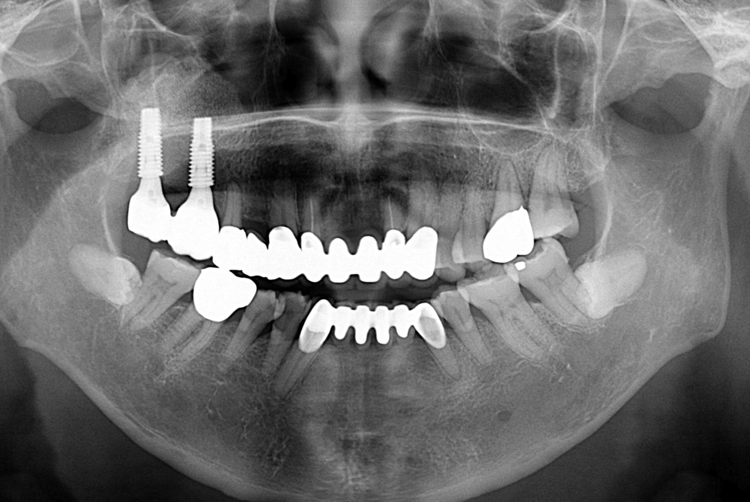

치료사례

세종치과의 진심 어린 치료는 결과로 말합니다.

실제 내원하신 환자분들의 치료 전·후 사례를 확인해보세요.

모든 치료사례 전후사진은 환자분의 동의하에 촬영되었습니다.

모든사진은 동일 환자분의 전후모습을 촬영하였으며, 사진의 밝기조절 외에 임의 수정이 없음을 알려드립니다.